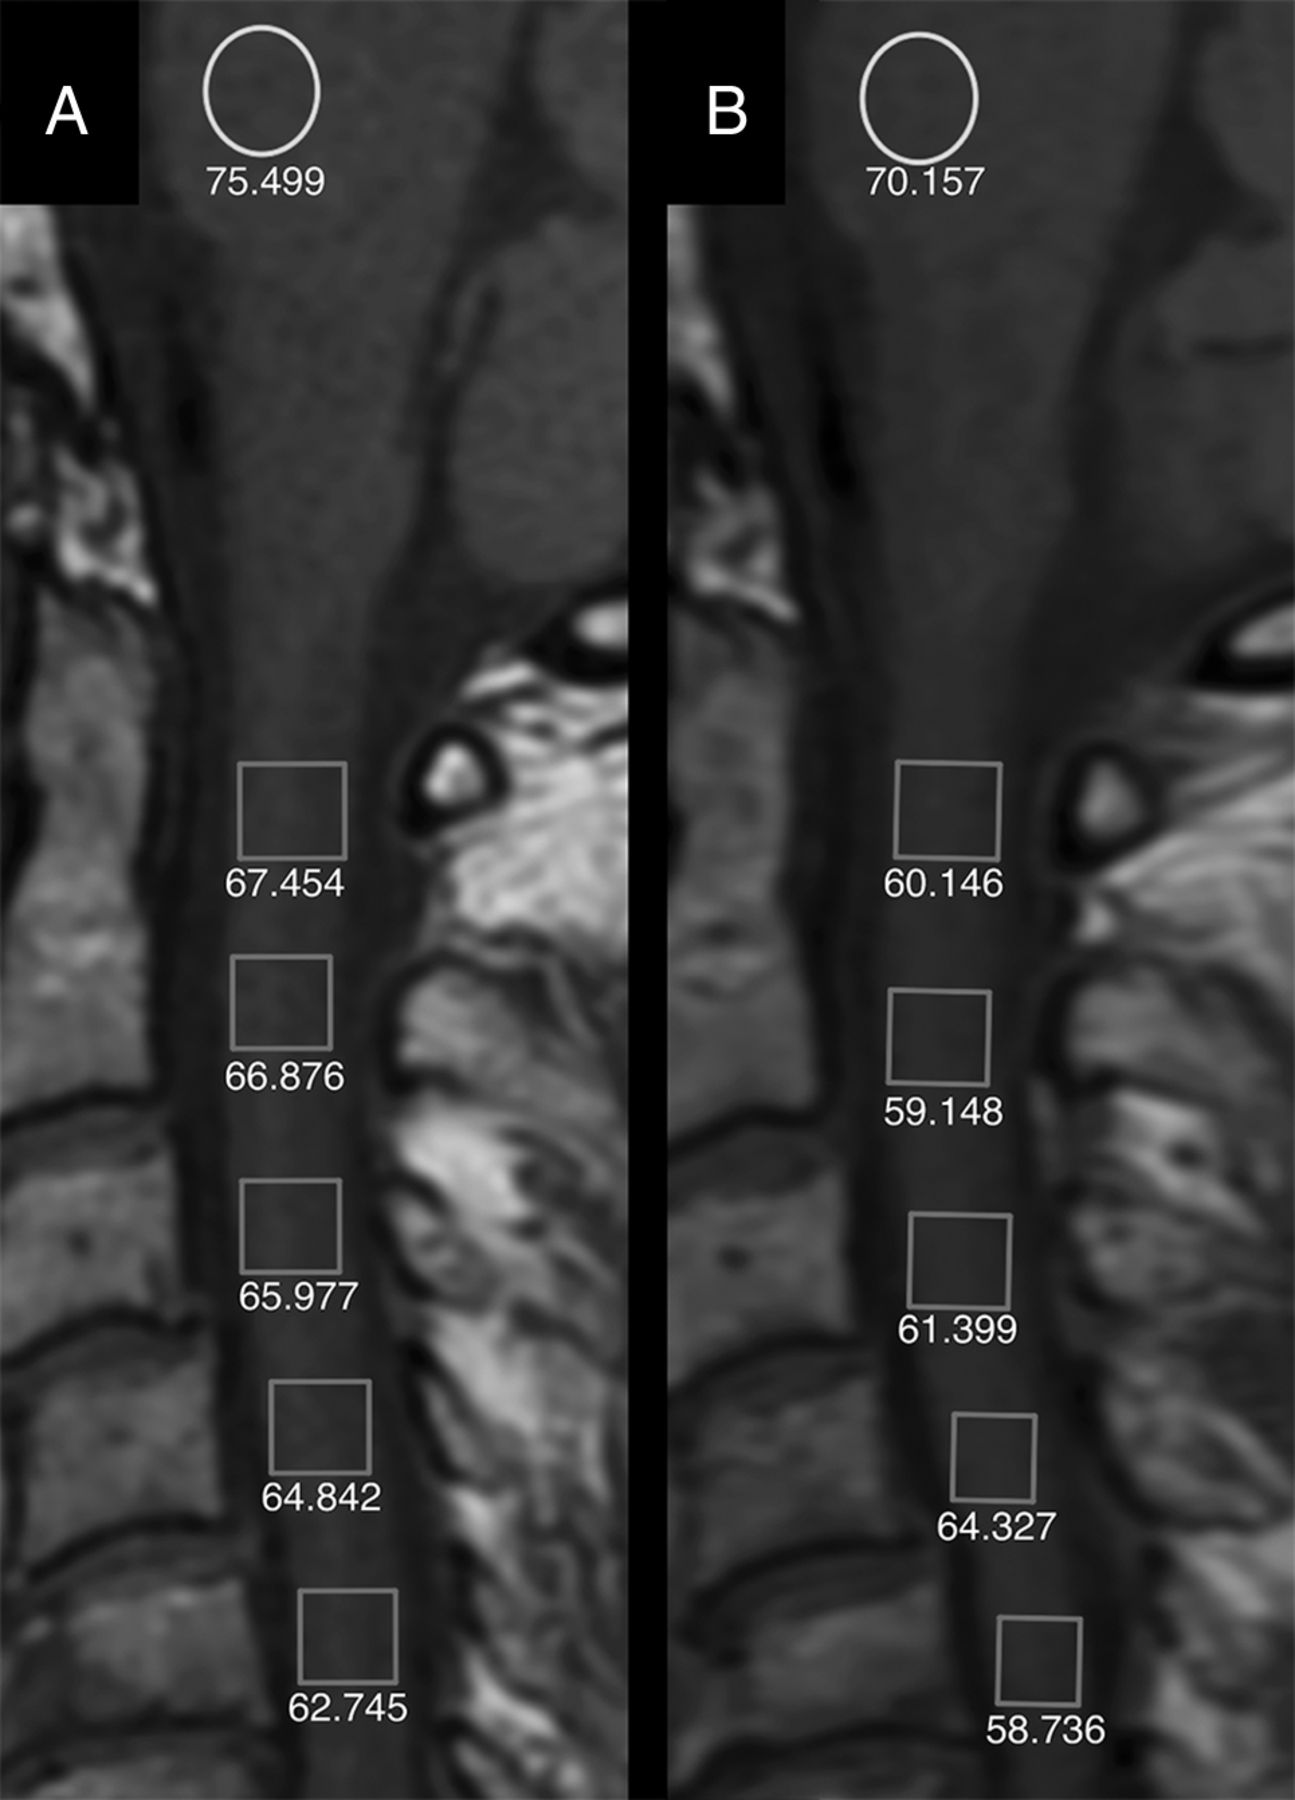

Unenhanced sagittal T1-weighted images at the first (A) and the ninth (B) contrast-enhanced MR imaging of a 57-year-old woman with relapsing-remitting multiple sclerosis treated with natalizumab. Rectangles are the ROIs placed from the C1 to C5 level. Circles are the ROIs in the pons. Absolute numbers of signal intensity measurements are reported for each ROI. The changes of the cervical spinal cord-to-pons signal intensity ratio between the first and the last MR imaging scans are not statistically different. TR = 650 ms; TE = 10 ms; section thickness = 3 mm; matrix = 192 × 256.

The CS-to-pons SI changes were found to be not significantly different from 0 (P = .400), with a mean value of +0.0008 ± 0.0089 (95% CI, −0.0011–0.0027) (Fig 5). The difference in the CS-to-pons SI between the first and last scan was not statistically significant in patients who had ≥6 injections compared with patients who had ≤5 injections (P = .565) (Fig 3). Furthermore, in both groups, the CS-to-pons SI changes were not significantly different between patients who received only Gd-BOPTA from the first to last scan compared with patients who had both Gd-BOPTA and Gd-DTPA injections (group A, P = .738; Group B, P = .906).

Regarding the spinal cord, rectangular ROIs covering the whole midline section of the spinal cord were placed at the C1, C2, C3, C4, and C5 levels on the unenhanced T1-weighted sagittal midline plane. The C6 and C7 levels were excluded from the analysis due to frequent artifacts in the lower CS. On the same slice, another ROI was placed on the pons. The CS-to-pons SI ratio was calculated by dividing the average signal of the 5 ROIs located in the CS by the signal of the pons.